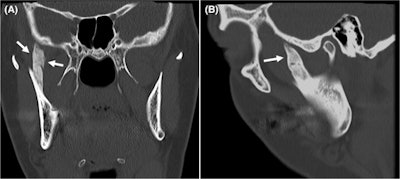

Four months after treatment, the woman presented with an inability to open her mouth. At that time, her mouth opening was 8 mm. The patient was unable to move her jaw laterally. She underwent a computed tomography (CT) scan, which showed an approximately 3-cm long bony growth that extended from the right coronoid process of the jaw to the cranial base, they wrote.

CT in the (A) frontal and (B) sagittal view shows ossification of the woman's right temporal muscle attachment extending to the cranial base (arrows). Images courtesy of Pedersen et al. Licensed by CC BY 4.0.